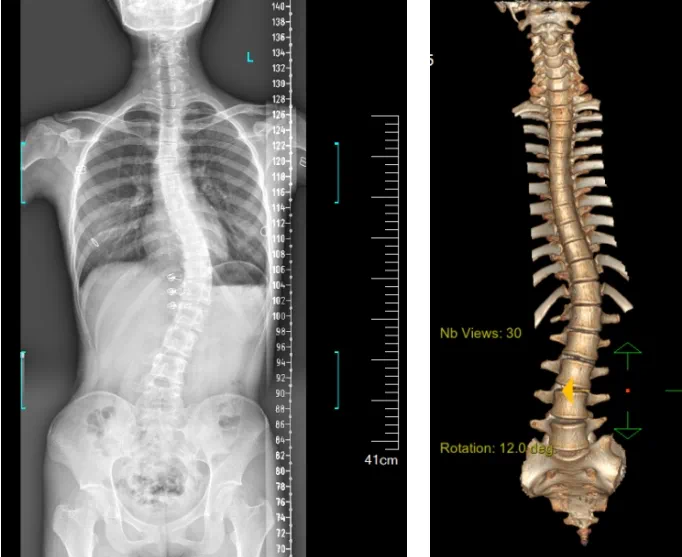

患者為一名16歲女孩,發現脊柱側彎1年,到南方醫院贛州醫院脊柱外科求診。經查體,患者左右胸廓不對稱,雙肩等高,左肩胛骨隆起,背側呈“剃刀背”畸形,胸腰段棘突偏離正中線,胸腰段脊柱左側凸畸形;各棘突無壓痛及叩擊痛,右側腰部凹陷,胸腹及腰背部感覺正常。檢查發現患者特發性脊柱側彎,Lenke5C型,主胸彎51°。患者及家屬對外觀不滿意,為改善外觀及功能,要求手術矯形治療。

在與患者及家屬充分溝通后,針對患者的病情,脊柱外科團隊在科主任陳榮春的指導下,經過術前仔細評估,制定了機器人輔助下脊柱側彎矯形、植骨融合內固定手術的治療方案,由郭朝陽主任醫師主刀實施。

據悉脊柱側彎手術治療后可以保持軀干平衡,改善外觀并防止畸形進一步發展。患者的生活質量得到提高,進而減少脊柱過度畸形可能帶來的疾病的發生率,外觀上的積極變化往往也能帶來患者心理與精神的積極變化。臨床上會綜合考慮患者的年齡、側彎程度、進展趨勢、骨質條件、鄰近節段情況、手術節段等因素,合理采用個性化的手術方式進行治療。然而,由于脊柱神經血管密布,手術操作相對復雜,手術難度高、風險大,傳統脊柱側彎的手術方式往往有較高的神經或脊髓損傷風險。故此次科室決定開展機器人輔助導航下脊柱側彎矯形、植骨融合內固定手術。術前,醫生團隊在機器人多維度圖像融合智能手術規劃功能的輔助下,預先規劃了理想的置釘路徑。術中,天璣骨科手術機器人準確遵循術前規劃,根據配準結果,實時定位并準確執行置釘操作,所有導針均用電鉆置入,一次性成功,協助醫生順利完成手術。最終,在麻醉科、手術室密切配合下,歷時3小時成功完成側彎矯形術,出血量僅500ml。術后,患者恢復良好,大小便及下肢神經運動感覺正常。